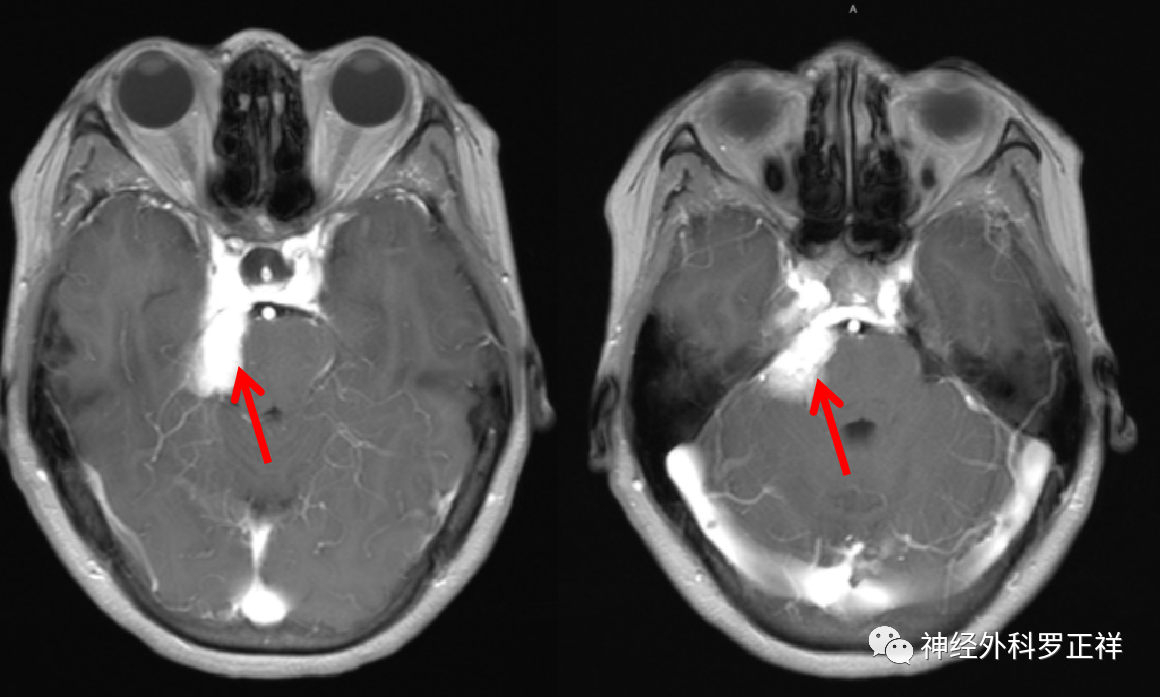

术前磁共振检查诊断:右侧岩尖脑膜瘤、继发性右侧TN;

术前MRI提示肿瘤位于右侧岩尖,压迫脑干及三叉神经。

术前磁共振轴位增强

术后增强示肿瘤全切